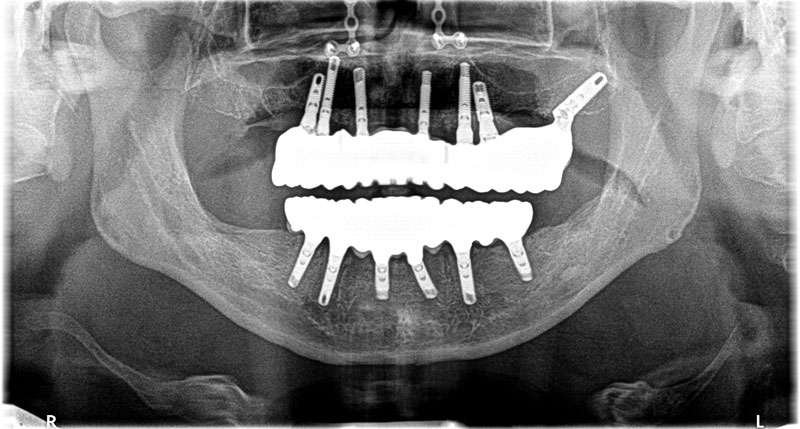

- 治療方針:上顎はインプラント7本による固定式13本ブリッジの装着。下顎はインプラント6本による固定式12本ブリッジの装着

- 上顎、鎮静、局所麻酔下で抜歯即時埋入6本、傾斜埋入1本行う。(鼻中湾曲を認め、左側は重度の慢性副鼻腔炎もわずらっていたため、ソケットリフトやサイナスリフト等の副鼻腔へのアプローチは回避した。)

- 下顎、鎮静、伝達局所麻酔下で抜歯即時埋入6本を行う。

- 3か月後インプラントが骨に定着したのを確認し(ISQ値75以上)、一時的に使用していた残存歯を抜歯、ソケットプリザベーションし、インプラントによる仮歯を装着。

- 2か月後、抜歯穴の状態が落ち着いてから、最終補綴の型、高さの検査を行い、ねじ止め式の上部構造(チタンフレーム使用+ジルコニア+ガムセラミック)をセット。

術後5年コメント

タバコも止められ、幸い危惧していた歯石の沈着も殆ど認められず、口腔衛生状態もいうことなし。ただ元々の歯周病タイプは、例え歯磨きが良好になったとしても、噛みしめや歯ぎしりといった習癖によるトラブル(中ねじの破損、インプラントの破損、ジルコニアやセラミックの破損等)の発生はあり得ることなので、できれば夜間のマウスピースの着用等は必須と個人的に考えています。